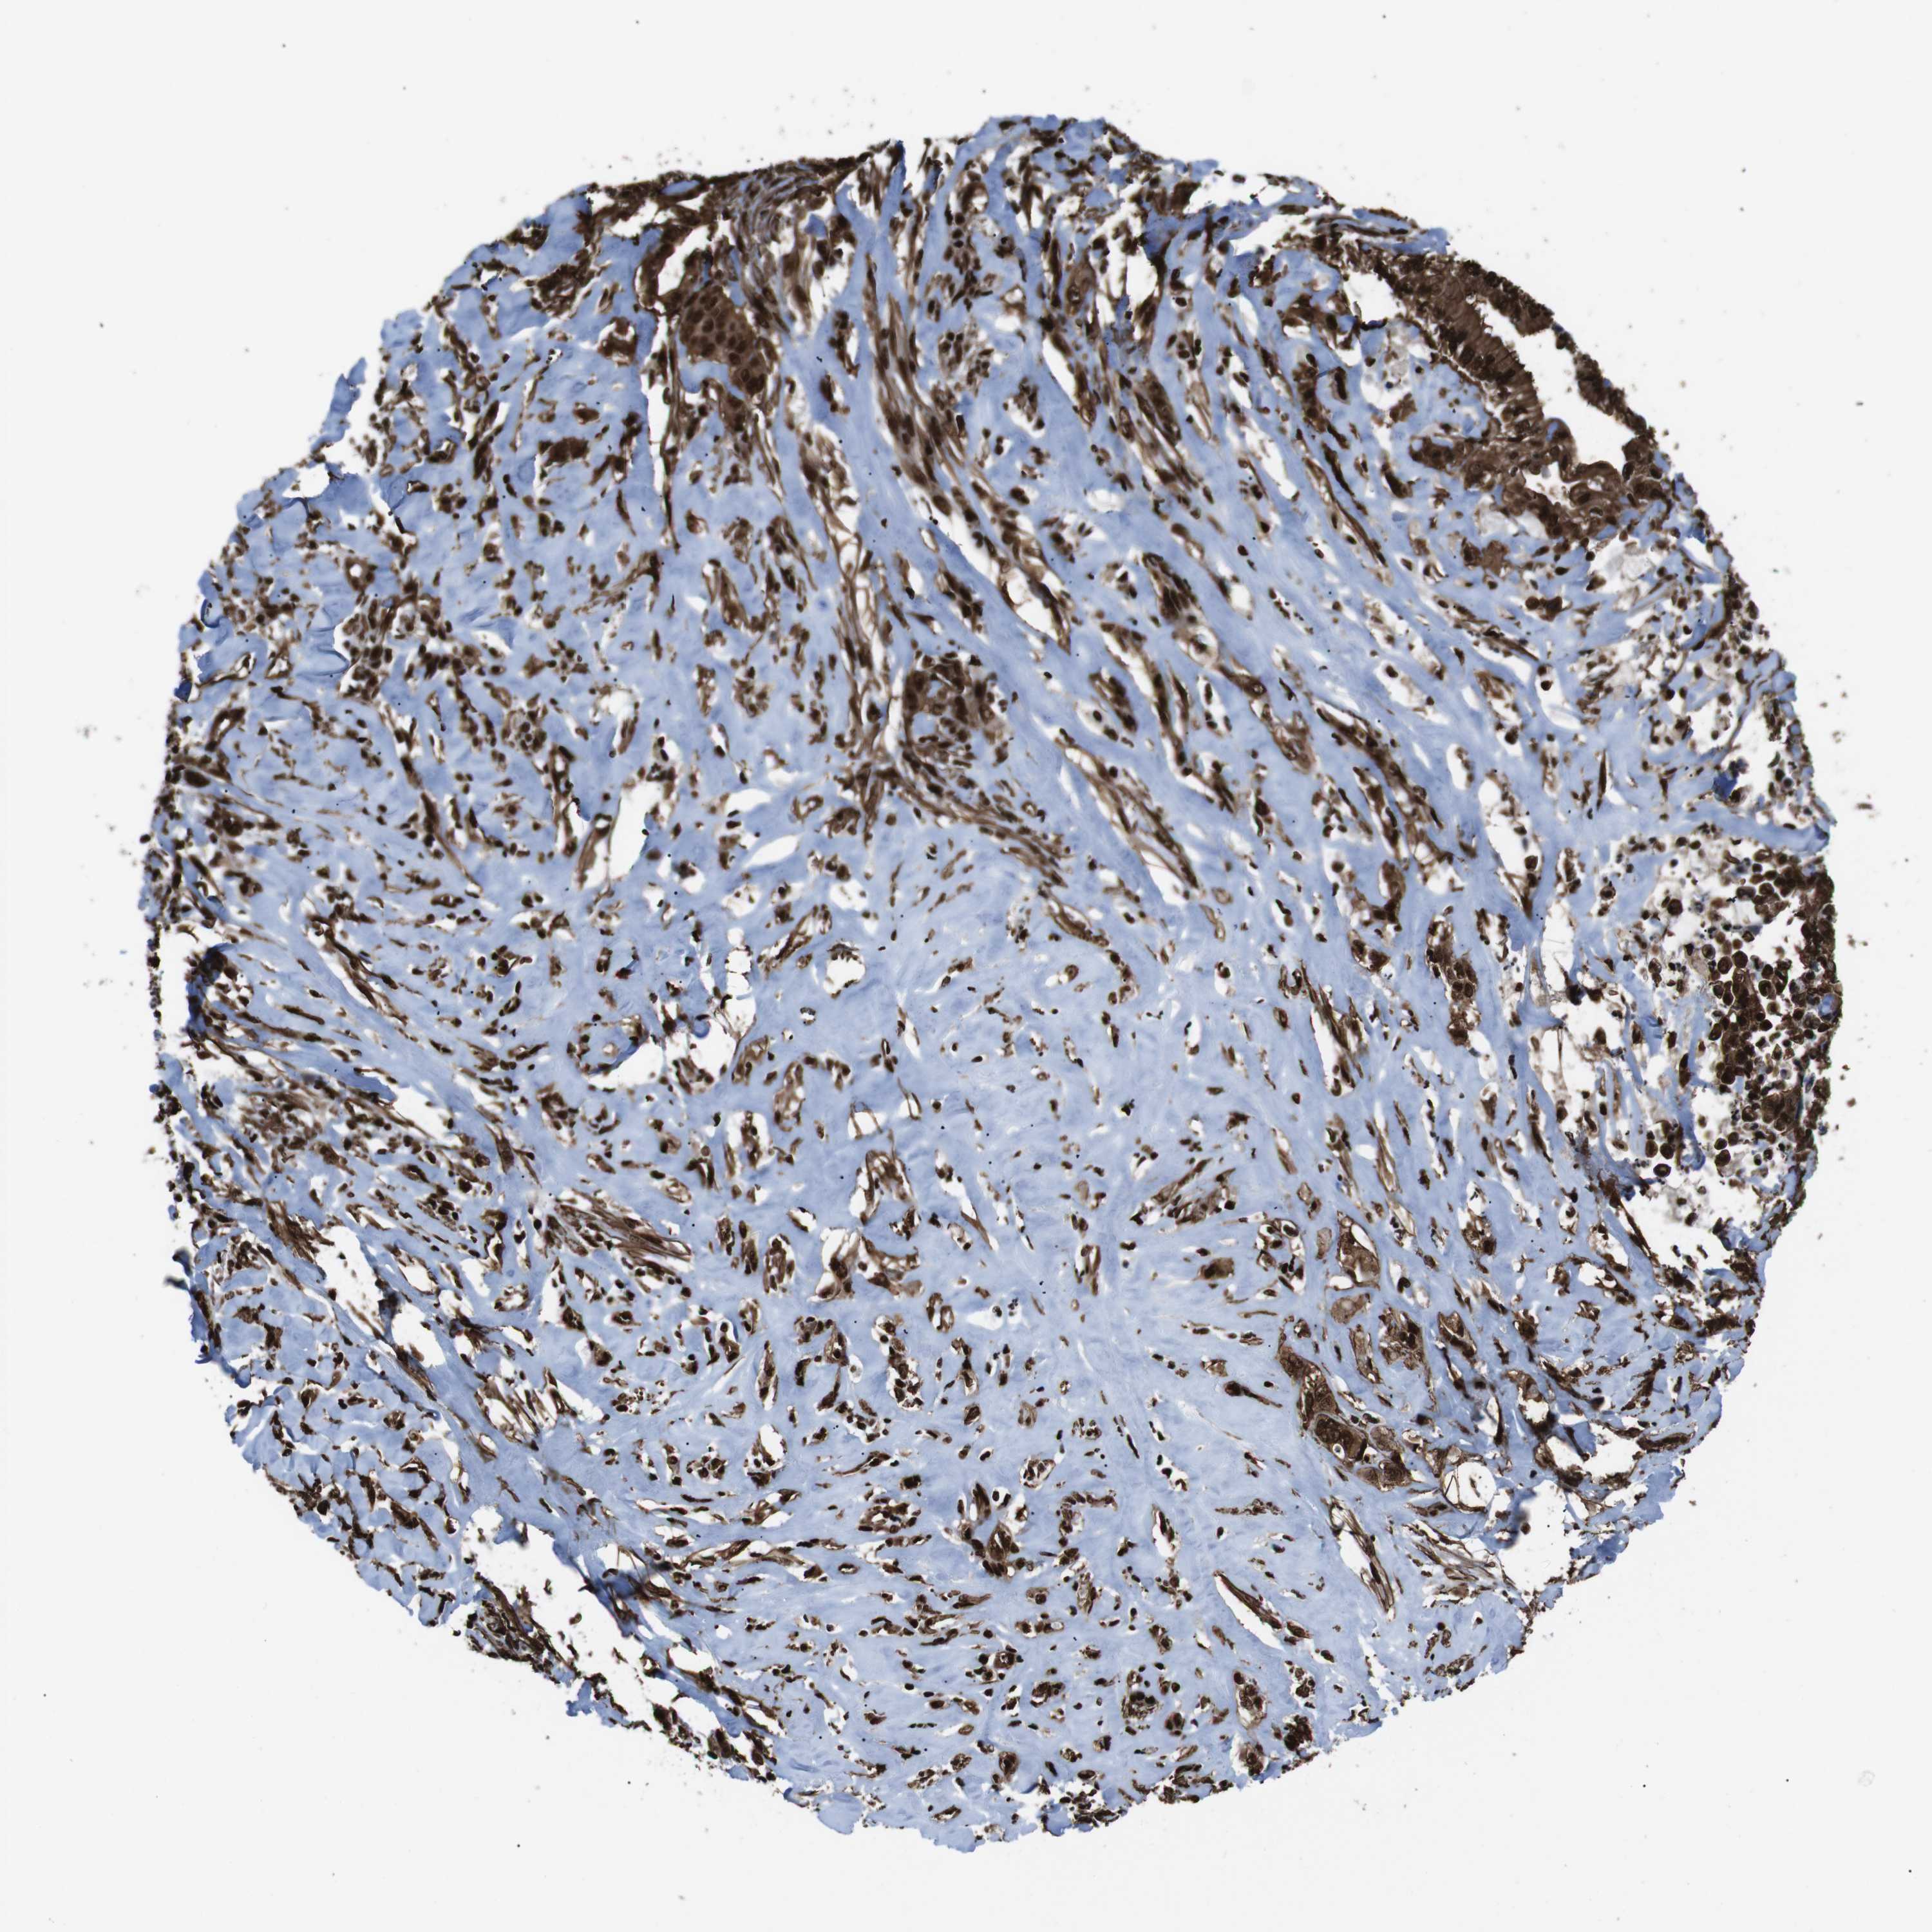

LIVER CANCER - Protein expressioni

A mouse-over function shows sample information and annotation data. Click on an image to view it in a full screen mode. Samples can be filtered based on level of antibody staining by selecting one or several of the following categories: high, medium, low and not detected. The assay and annotation is described here.

Note that samples used for immunohistochemistry by the Human Protein Atlas do not correspond to samples in the TCGA dataset.

Antibody stainingi

Antibody staining in the annotated cell types in the current human tissue is reported as not detected, low, medium, or high, based on conventional immunohistochemistry profiling in selected tissues. This score is based on the combination of the staining intensity and fraction of stained cells.

Each image is clickable and will lead to virtual microscopy that enables deeper exploration of all samples and also displays staining intensity scores, fraction scores and subcellular localization as well as patient and tissue information for each sample.

Antibody HPA041057

Antibody HPA058707

Antibody CAB011532

Staining

High

Medium

Low

Not detected

Intensity

Strong

Moderate

Weak

Negative

Quantity

>75%

75%-25%

<25%

None

Location

Nuclear

Cytoplasmic/membranous

Cytoplasmic/membranous,nuclear

Cholangiocarcinoma

Carcinoma, Hepatocellular, NOS